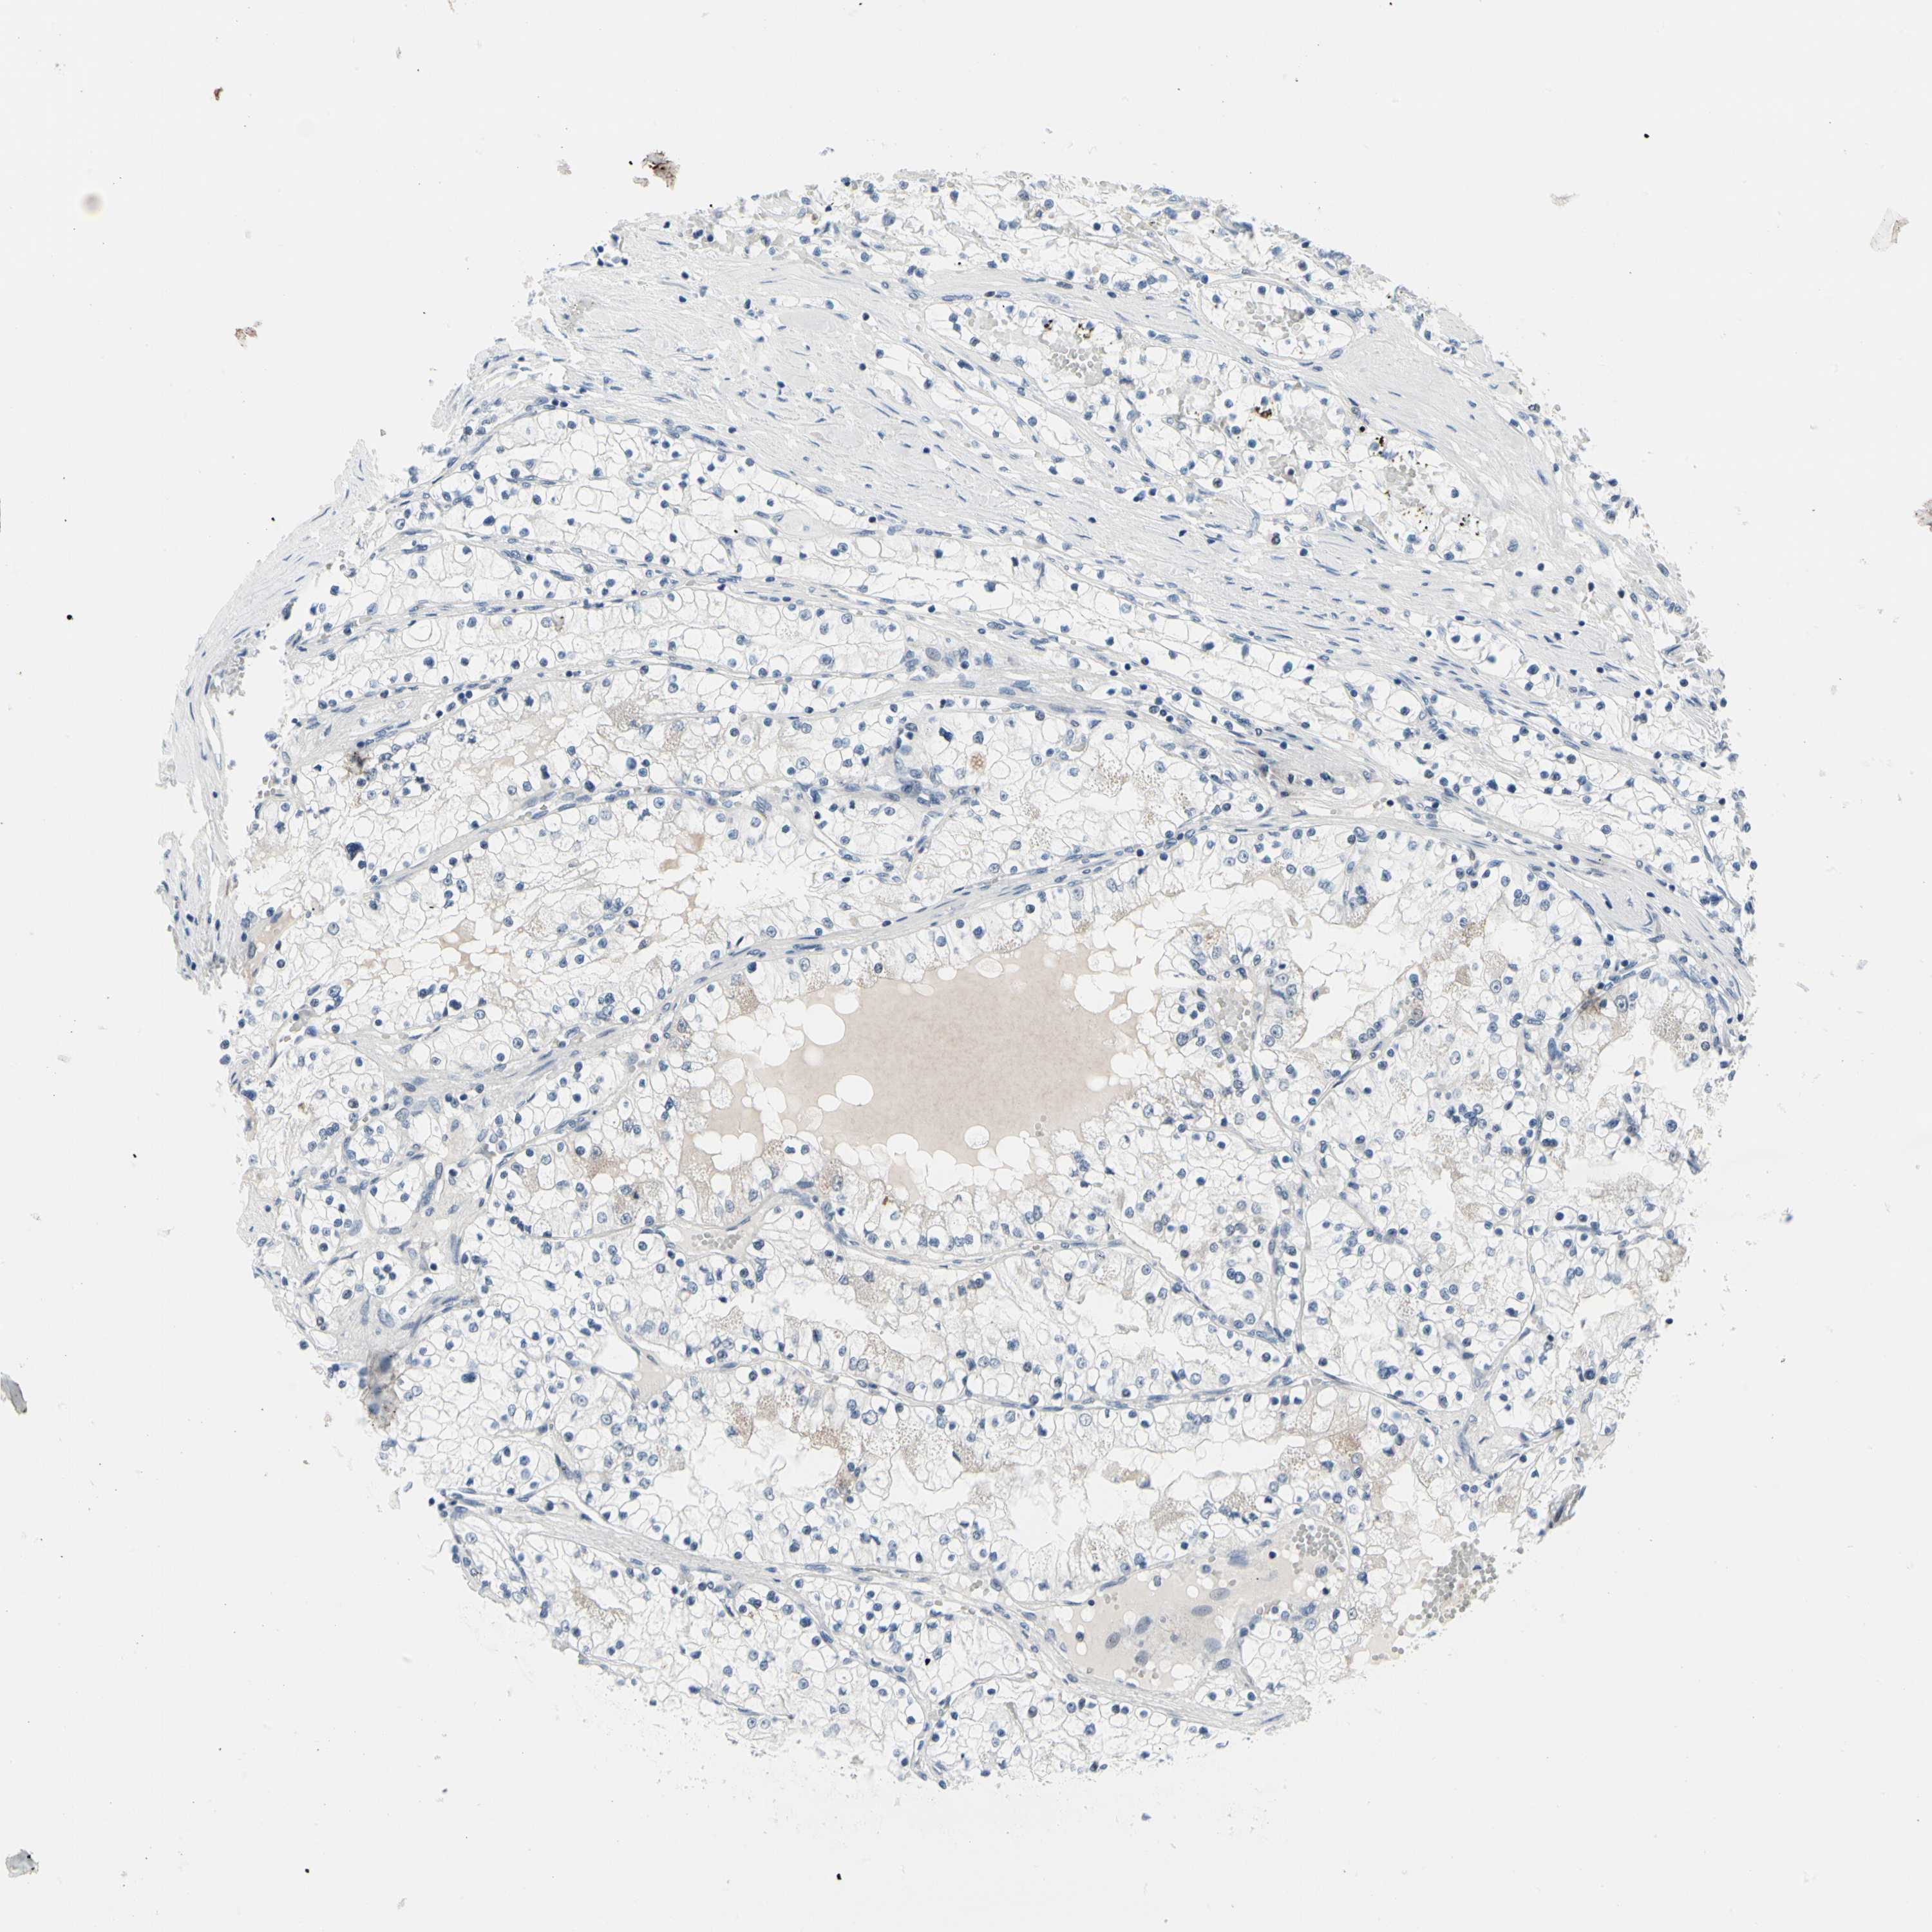

KIDNEY RENAL CLEAR CELL CARCINOMA (VALIDATION) - Interactive survival scatter ploti

The Survival Scatter plot shows the clinical status (i.e. dead or alive) for all individuals in the patient cohort, based on the same data that underlies the corresponding Kaplan-Meier plots. Patients that are alive at last time for follow-up are shown in blue and patients who have died during the study are shown in red.

The x-axis shows the expression levels (FPKM) of the investigated gene in the tumor tissue at the time of diagnosis. The y-axis shows the follow-up time after diagnosis (years). Both axes are complimented with kernel density curves demonstrating the data density over the axes. The top density plot shows the expression levels (FPKM) distribution among dead (red) and alive patients (blue). The right density plot shows the data density of the survived years of dead patients with high and low expression levels respectively, stratified using the cutoff indicated by the vertical dashed line through the Survival Scatter plot. This cutoff is automatically defined based on the FPKM cutoff that minimizes the p-score. The cutoff can be changed by dragging the vertical line or by entering a cutoff value in the square labeled "Current cut-off".

Under the Survival Scatter plot the p-score landscape (black curve; left axis) is shown together with dead median separation (red curve; right axis). Dead median separation is the difference in median mRNA expression between patients who have died with high and low expression, respectively. It is calculated as follows: median FPKM expression of dead patients with high expression - median FPKM expression of dead patients with low expression. This is intended to aid the user in visually exploring custom cutoffs and the associated p-scores and dead median separation.

Individual patient data is displayed and can be filtered by clicking on one or more of the category buttons on the top of the page. Categories describing expression level and patient information include: high, low, alive, dead, female, male and tumor stages. The scale of the x-axis can be toggled between linear and log-scale by clicking on the "x log" button. Mouse-over function shows TCGA ID, patient information and mRNA expression (FPKM) for each patient.

& Survival analysisi

Kaplan-Meier plots summarize results from analysis of correlation between mRNA expression level and patient survival. Patients were divided based on level of expression into one of the two groups "low" (under cut off) or "high" (over cut off). X-axis shows time for survival (years) and y-axis shows the probability of survival, where 1.0 corresponds to 100 percent.

TXN is not prognostic in Kidney Renal Clear Cell Carcinoma (validation)

Best expression cut offi

Based on the FPKM value of each gene, patients were classified into two groups and association between prognosis (survival) and gene expression (FPKM) was examined. The best expression cut-off refers the FPKM value that yields maximal difference with regard to survival between the two groups at the lowest log-rank P-value. Best expression cut-off was selected based on survival analysis .

When clicking on this number, the vertical dashed line indicating cut-off, the interactive survival plot, and the Kaplan-Meier curve will be adjusted to show results based on the best expression cut-off.

: 410.84

Median expressioni

Median expression refers to the median FPKM value calculated based on the gene expression (FPKM) data from all patients in this dataset. When clicking on this number, the vertical dashed line indicating cut-off, the interactive survival plot, and the Kaplan-Meier curve will be adjusted to show results based on the median expression.

: N/A

Median follow up timei

Median follow up time refers to the median time (years) after diagnosis with this type of cancer, based on clinical data from all patients in this dataset.

P scorei

Log-rank P value for Kaplan-Meier plot showing results from analysis of correlation between mRNA expression level and patient survival.

N/A

5-year survival highi

5-year survival for patients with higher expression than the expression cutoff.

For melanoma and glioma, 3-year survival is shown.

5-year survival lowi

5-year survival for patients with lower expression than the expression cutoff.

TCGA RNA samplesi

RNA-seq data is reported as average FPKM (number Fragments Per Kilobase of exon per Million reads), generated by the The Cancer Genome Atlas (TCGA) .

Normal distribution across the dataset is visualized with box plots, shown as median and 25th and 75th percentiles. Points are displayed as outliers if they are above or below 1.5 times the interquartile range. FPKM values of the individual samples are presented next to the box plot.

Average pTPM 322.3

Number of samples 100